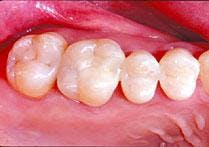

Regarding posterior composites, all - and I mean all - decay and soft dentin and decalcified enamel must be removed. This is a zero-tolerance consideration!

There is no toxic biofilm to save you here. Bonding has to be precise! Bonding over an unknown micro-junk pile - similar to current "sealant" theory - is a fantasy fix. No amount of sixth - or any generation - agent will help you, nor will a high-output laser help you. You are on your own, chum!

There is no place for poorly done posterior composites. Amalgam succeeded because it was toxic and technique-insensitive. But now, with some effort, we can do better.